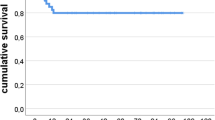

Continuous variables were reported as mean ± standard deviation (SD) and compared between pre-operative and final follow-up using the Student t test. Categorical variables were expressed as the number of cases or percentage. For all the analysed data, a two-tailed, p value < 0.05 was considered statistically significant. Inter-observer reliability was evaluated with the Cohen’s kappa coefficient. Kaplan-Meier survival curves with 95% confidence intervals (CI) were created to analyse custom-made implant survivorship free of revision for any reason as the endpoints. We defined as re-operation any kind of surgery that involved the hip joint after the index procedure without removing the custom acetabular component. Conversely, revision was considered as any surgical procedure that required custom implant removal for any reason. We defined septic recurrence as each new infection or positive culture at re-implantation with isolation of the original infecting organism.

In this study, the mean rate of custom acetabular AL was 0% with an overall custom implant survival rate of 95% as demonstrated by Kaplan-Meier analysis (Fig. 4). The mean rate of re-operations and re-revisions were 10% and 5%, respectively. Despite being a difficult reconstructive challenge in a patient population that often has multiple previous surgeries and comorbidities, our study shows promising outcomes in terms of clinical improvement expressed as Harris Hip Scores, Oxford Hip Score, and the Visual Analogue Pain Score.

In a recent systematic review, the mean rate of aseptic loosening and survivorship of custom acetabular was 2.6 ± 4.0% and 94.0 ± 5.0%, respectively, with an average follow-up of 58.6 months. The mean reported rates of re-operation and re-revision were 19.3% and 5.2%, respectively.